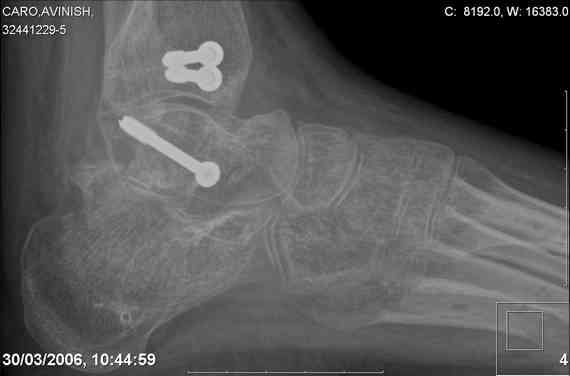

ya by popytalsya sobrat talus anatomichno,seichas pozdno operirovat iz za oteka,po etomy distrakziya apparatom budet optmalna.Posyalu vam podobyai moi sluchai.

14 years old girl

Fall from height ( 3rd floor)